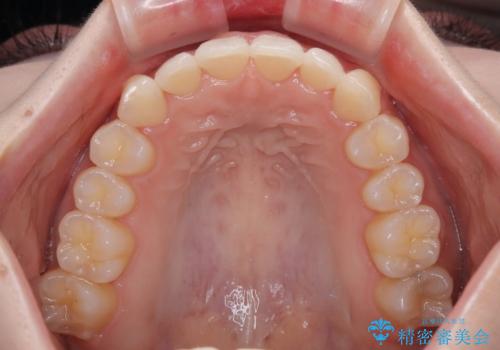

前歯が隠れるほどのデコボコをインビザライン矯正できれいに整える

- 前歯のデコボコを気にして来院された患者様です。

全体的にデコボコが多く、特に下の前歯は隠れてしまうほどの状態でした。

左右ともに奥歯の咬み合わせが理想的な位置にあったこともあり、患者様のご希望通り、インビザラインにて矯正治療を行うこととしました。

マウスピース矯正特有の、奥歯が噛みにくくなるという現象の解消に少し期間をいただきましたが、日々の装着時間を遵守していただき、綺麗な歯列に整えることができました。